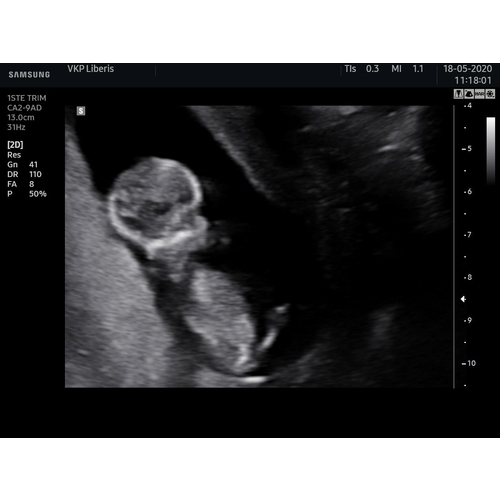

Onze Eerste Echo Zwanger Na Icsi Behandeling

Eerste Echo Na Icsi Spannend Zwangerschapspraat 24baby Nl Forum